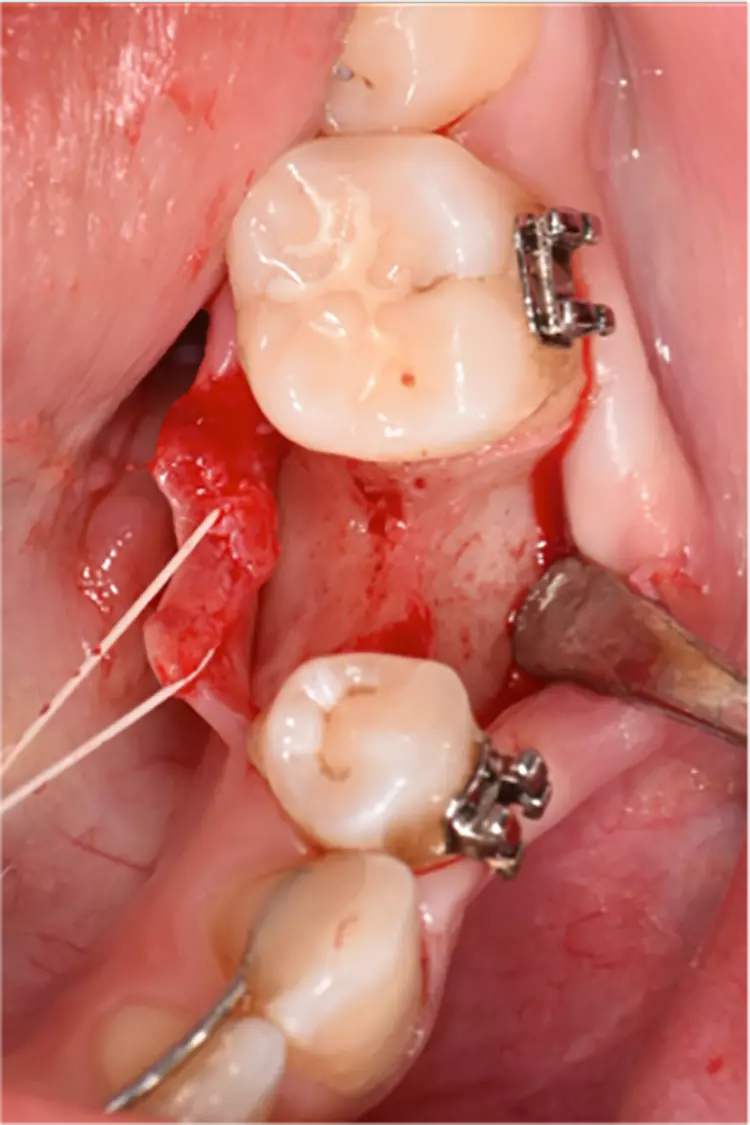

Die Implantate wurden im üblichen chirurgischen Vorgehen inseriert und sofort mit einem Provisorium aus Polymethylmethacrylat (CAD-Temp, VITA) versorgt, wobei die Provisorien außer Okklusion geschliffen wurden und darauf geachtet wurde, dass approximal nur sehr schwache Kontakte bestanden (Abb. 3a bis e). Die definitive prothetische Versorgung erfolgte im Unterkiefer nach frühestens 2 Monaten, im Oberkiefer nach frühestens 4 Monaten. Die Restaurationen wurden aus verblendetem Zirkonoxid hergestellt (VITA YZ HT / VITA VM 9, VITA).

Bei Knochendefekten ist eine Augmentation erforderlich. In der klinischen Studie „FR/ZH“ wurden in 11 Fällen kleinere simultane Augmentationen durchgeführt (vergl. Abb. 3). Die Augmentationen dürfen aufgrund der ermittelten Sondiertiefen und Röntgenbefunde als erfolgreich angesehen werden.

Es wurden Bone-Level-Prototypen-Implantate auf der Basis des ceramic.implant verwendet. Nach deren Implantation wurde die bukkale Knochenwand entfernt. Die Knochendefekte wurden mit bovinem Knochenersatzmaterial (Bio-Oss, Geistlich Pharma, Wolhusen, Schweiz) verschiedener Darreichungsformen gefüllt, mit einer Kollagenmembran (Bio-Gide, Geistlich Pharma) abgedeckt und mit der Mukosa verschlossen.

Es gab nach 3 Monaten keine signifikanten Unterschiede zwischen den einzelnen Gruppen in Bezug auf den neugebildeten Knochen, das Knochenersatzmaterial und das nicht-mineralisierte Gewebe innerhalb des gesetzten Defektes. Augmentationsmaterial in Granulatform ? abgedeckt mit einer Kollagenmembran – hat für Zirkonoxidimplantate die besten Resultate im Hinblick auf den Erhalt der Knochenkontur geliefert. Die Resultate waren vergleichbar mit einer Kontrollgruppe, bei der Titanimplantate verwendet wurden.